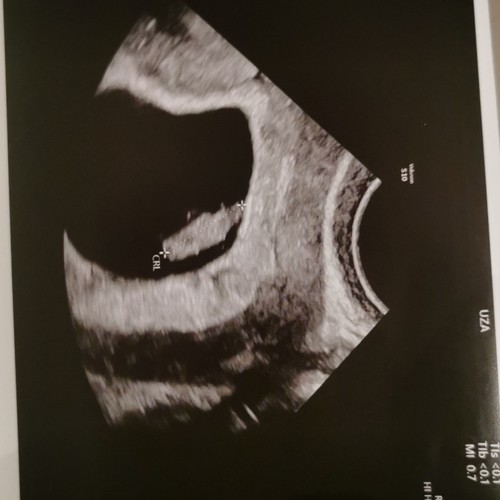

Dit was mijn echo 5+5 ( er staat geloof ik ander termijn op , ik was echt veel terug gezet, door een gemiste menstruatie die dus eigenlijk gewoon gemist was en geen zwangerschap was )

Ze twijfelden wel of het goed zat, want groeide eerst ook niet lekker, met 7 weken terug gegaan voor een echo en het was gewoon gegroeid en zit prima ! Onderhand 30+4 van ons mannetje !